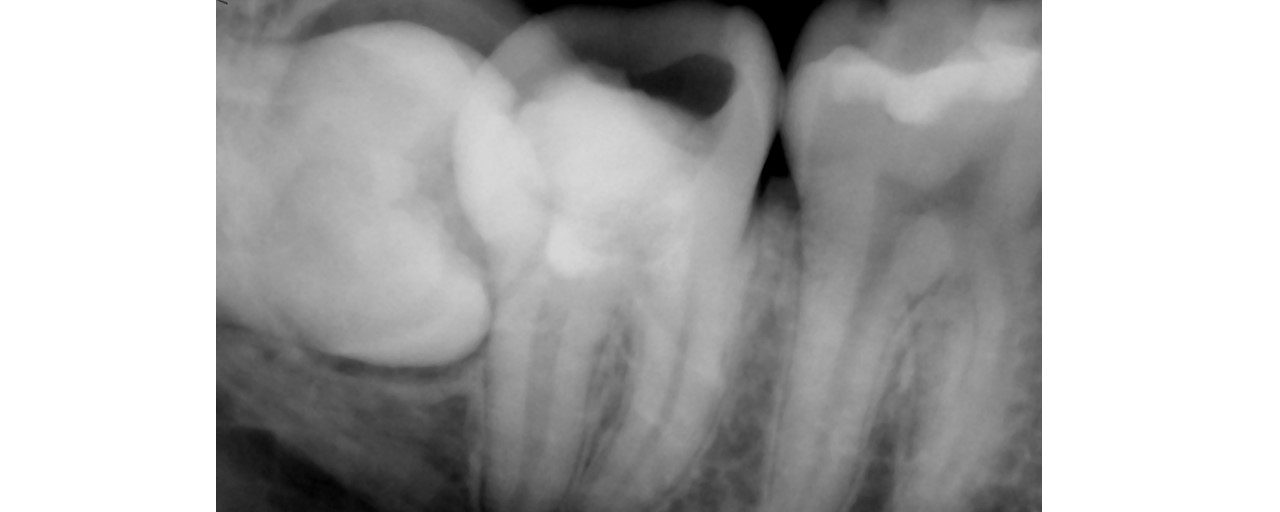

Selective Re-treat of Missed MB2